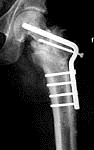

Here is an interesting case... 32 year old laborer s/p fall from 2 story window with femoral shaft fx treated with IM Rodding succesfully and a femoral neck fx treated with DHS and supplementary 7.3 cannulated screw fixation which went on to nonunion.

The nonunion was fixed with intertroch osteotomy

Now 7 months postop with impending failure of fixation (proximal migration of blade).

the options are repeat internal fixation with plate or rod device and my choice would depend on preoperative planning and templating. I don't think i would consider replacement in this young patient without giving repeat fixation at least one more try. Replacement might have to be a calcar replacing prosthesis with a long stem to avoid the stress risers from the screw holes and may not last long in a 30 year old. I don't see any signs of AVN on these xrays and i would only consider replacement at this point if there was collapse from AVN.

i would also have a high index of suspicion for infection. the first surgery probably failed because the femoral neck was fixed in varus which is not biomechanically advantatgeous obviously, and probably had poor bone contact with relatively poor fixation with the screws in the superior head. the fixation was probably not rigid. However the second procedure looks like a nice osteotomy with restoration of the biomechanics and at least stable fixation so i would be concerned that the failure this time was due to a subacute occult infection. Take cultures and even frozen sections for pathology just as you'd do with a loose hip replacement to be sure there is not infection. (even if there is infection, i would refix it to provide a stable environment for bone healing.)

Fig 7 is dramatically different from fig 9. It appears to me that a subcapital femoral neck fracture has occurred around the fixation. You may now have 4 major fragments (head, neck, peritroch, shaft). A hip fusion would most likely fail due to the avascular segments (head, neck). A hemi-arthroplasty or arthroplasty may be your only choice, but what a choice in a 32 year old laborer. Have the patient get voc rehab, change jobs, plan on sedentary life and take away his pain with arthroplasty after w/u for infection when it gets bad.

It seems the biology for this case is not active. Any metabolic source should be ruled out. The next thing to consider is whether the head is alive or not. MRI/bone scan or craig needle bviopsy should be helpful as well as a culture of the biopsy to rule out infection...\ESR and CRP also.

On occasion I have had a blade fail despite good biomechanics (probably due to lack of fracture site compression) and if the head is alive, and without infection, one should consider a Valgus (say 150 degree and antirotation screw with fresh iliac bone graft. Depending on one's philosophy, internal or external electric stim may be selected as an adjunct.

The fourth radiograph of the intra-operative series tells the story of the amount of compression generated by the use of the implant.

Not any STATIC compression! In this intra-operative radiograph, a clamp is shown holding the plate against the bone in the proximal region of the plate- osteotomy interface. This is an open angled plate and compression must be obtained by "mismatch", I challenge you, assuming good bone, what is the theoretical limit of compression - tension "Newtonian effects" that can be obtained by mismatch fixation with an open angled plate and screws in this situation. I can come up with 4 different effects...all synergetic to the overall effect of compression of bone surfaces !

which in this case enters the region of the neck nonunion and can only have a negative effect on bone that would like to heal.

Finally from what you showed us it looks like somewhere we picked up a fracture of the posterior neck, and the head contour is not looking normal...other than that from these radiograms, my vote is that it is healed!